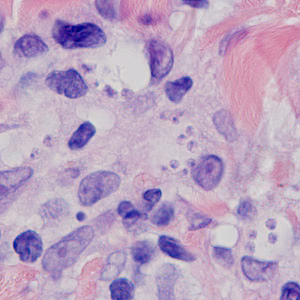

A 25-year-old female presented to a dermatologist with ulcerative lesions on her left arm and both lower legs. She had traveled to Panama three months prior. A biopsy specimen was obtained and sent to Pathology where it was sectioned and stained with hematoxylin and eosin (H&E). Figures A–D show what was observed at 1000x magnification with oil. What is your diagnosis? Based on what criteria? What, if any, other testing would you recommend?

Figure A